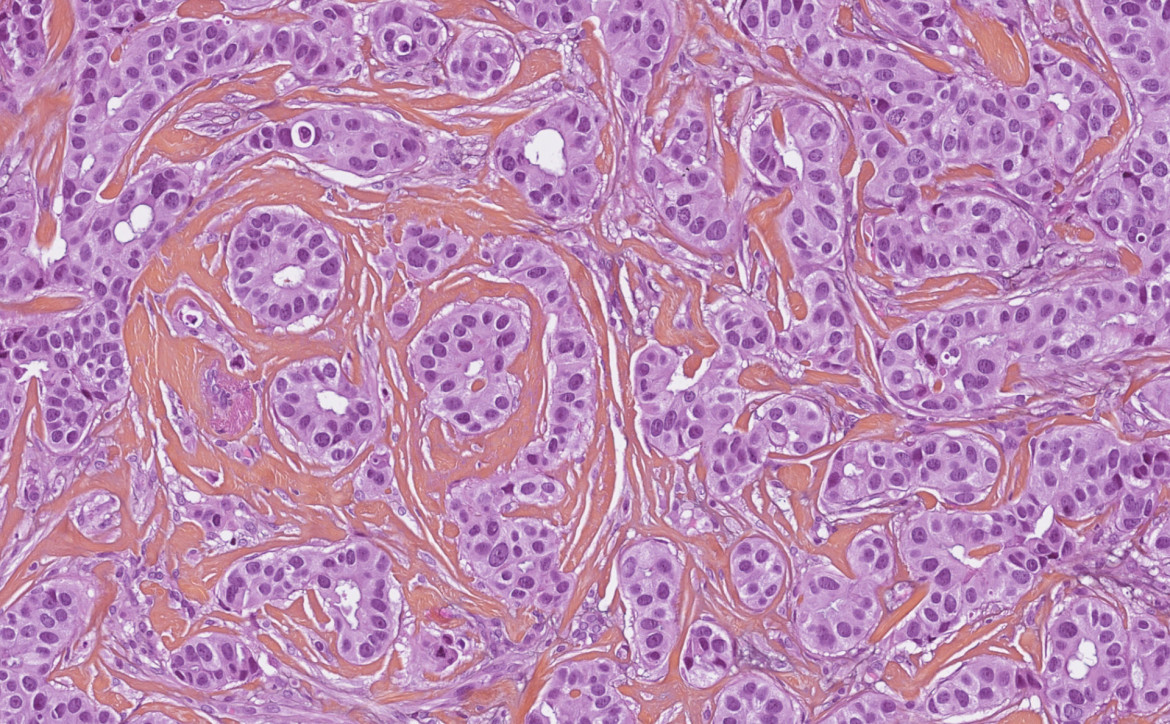

Les différents prélèvements subissent ensuite de multiples étapes techniques (fixation en formol, déshydratation, inclusion en paraffine, coupe au microtome), réalisées par les techniciens de laboratoire, s’effectuant sur plusieurs jours. Ces étapes permettent d’obtenir au final des coupes très fines (3 ou 4 microns d’épaisseur), colorées ("colorations standards" : Hématoxyline Eosine Safran - HES - à l’ICM), posées sur des lames de verres et observables au microscope.

Un des médecins pathologistes de l’institut, expert en cancérologie, examine ces lames au microscope (examen microscopique) et doit déterminer :